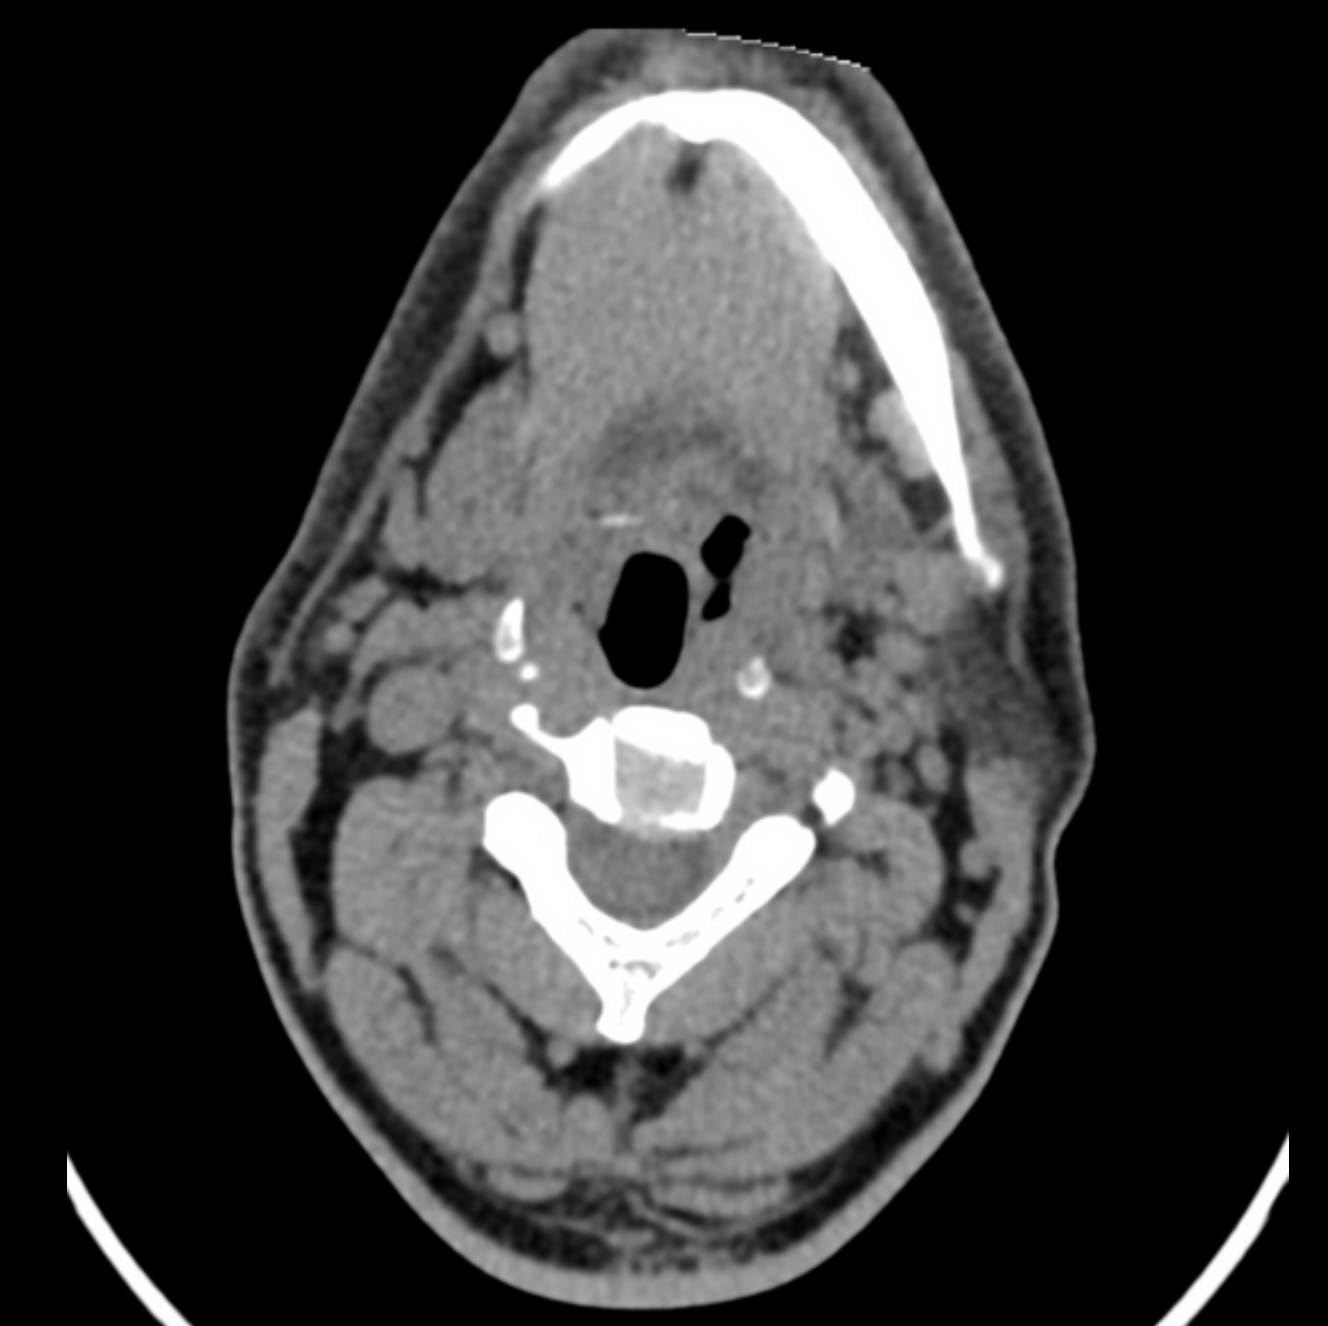

AI in daily radiology

Chest X-ray triage, fracture detection, mammography screening — studies flow from PACS, get processed, and results come back as DICOM Structured Reports and HL7 messages to RIS.